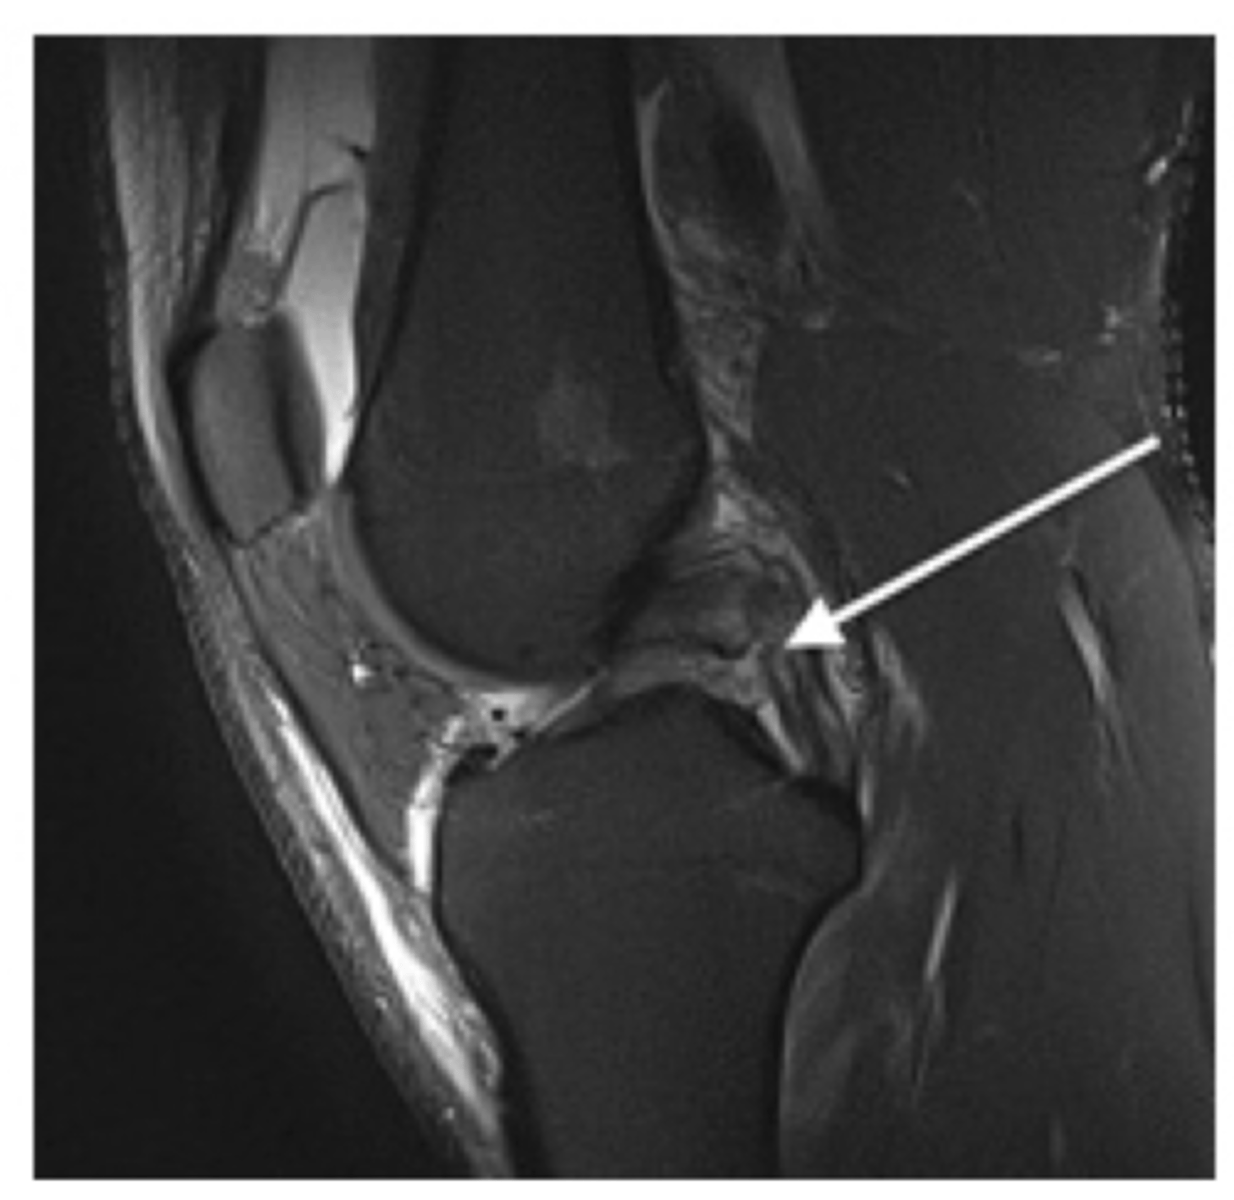

PCL (runs from posterior & inferior --> to anterior & superior)

Which structure is the white arrow pointing too?

Tear of the PCL -- normally, ligaments are pulled taut and appear straight; if they are torn, they appear wavy and/or curved over

Define the pathology. How do you know?